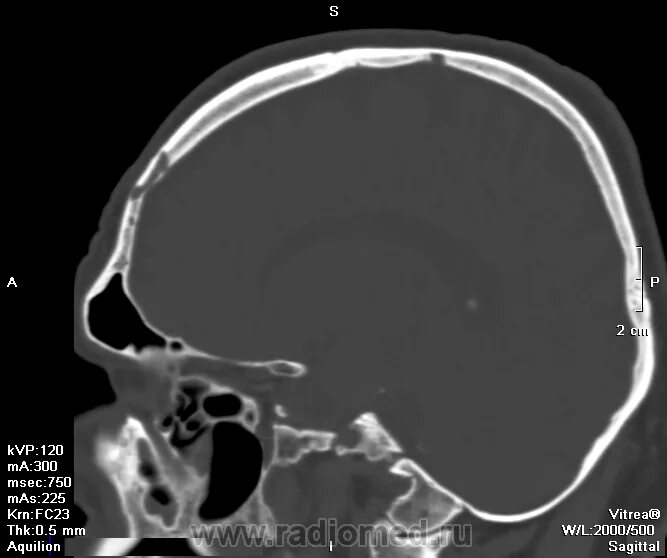

Череп на кт